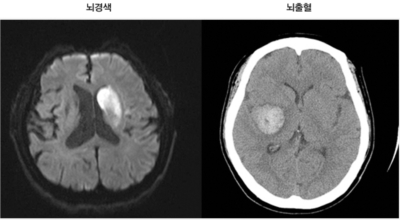

뇌경색이란

뇌 속에 혈액을 제공하는 혈관이 있는데, 이 혈관이 막히면 정상적으로 지급되어야 할 만큼의 혈액이 뇌까지 도달하지 못하여 뇌조직이 제 역할을 수행하지 못하는 것을 말해요. 이 시간이 지속될 경우 몸의 여러 곳에 지장이 생기며 이것을 뇌경색이라고 해요.

뇌경색의 주된 원인은 혈전입니다. 혈전이란 혈관 속에 피가 굳어진 덩어리를 얘기하는데 이것이 혈관을 막는 것이 뇌경색에 큰 영향을 준다고 해요. 평균적으로 많이 나타나는 연령대는 5~60대입니다. 뇌경색은 양쪽 뇌에 모두 생기는 것이 아니라 주로 한쪽 뇌에만 발생하지만, 주로 한쪽 팔다리가 마비되거나 얼굴 근육이 굳어버리기도 해요.

뇌경색이 생기는 원인은 아주 다양해요. 뇌경색은 뇌의 혈관이 막혀 뇌의 일부가 죽는 질병을 말하는데 주로 뇌경색의 원인은 혈전이며, 혈전으로 인해 뇌혈관이 막히는 위험 인자는 혈전을 발생하게 해요. 또한 동맥경화나 심장병, 혈관박리, 뇌혈관 기형 등으로 말미암아 생기게 될 수 있다고 하며 대부분이 60세 이상의 고령층에서 빈번히 나타나는 질환으로 알려져 있답니다.